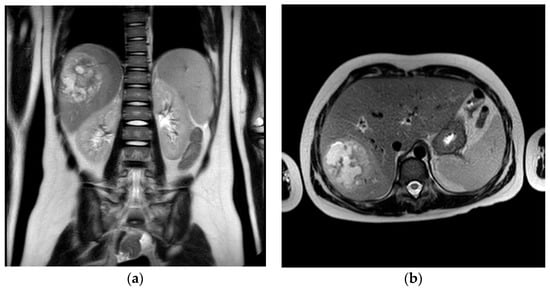

2.1. Case One—Liver Abscess

2.1.2. Initial Assessment and Hematological and Radiological Investigations